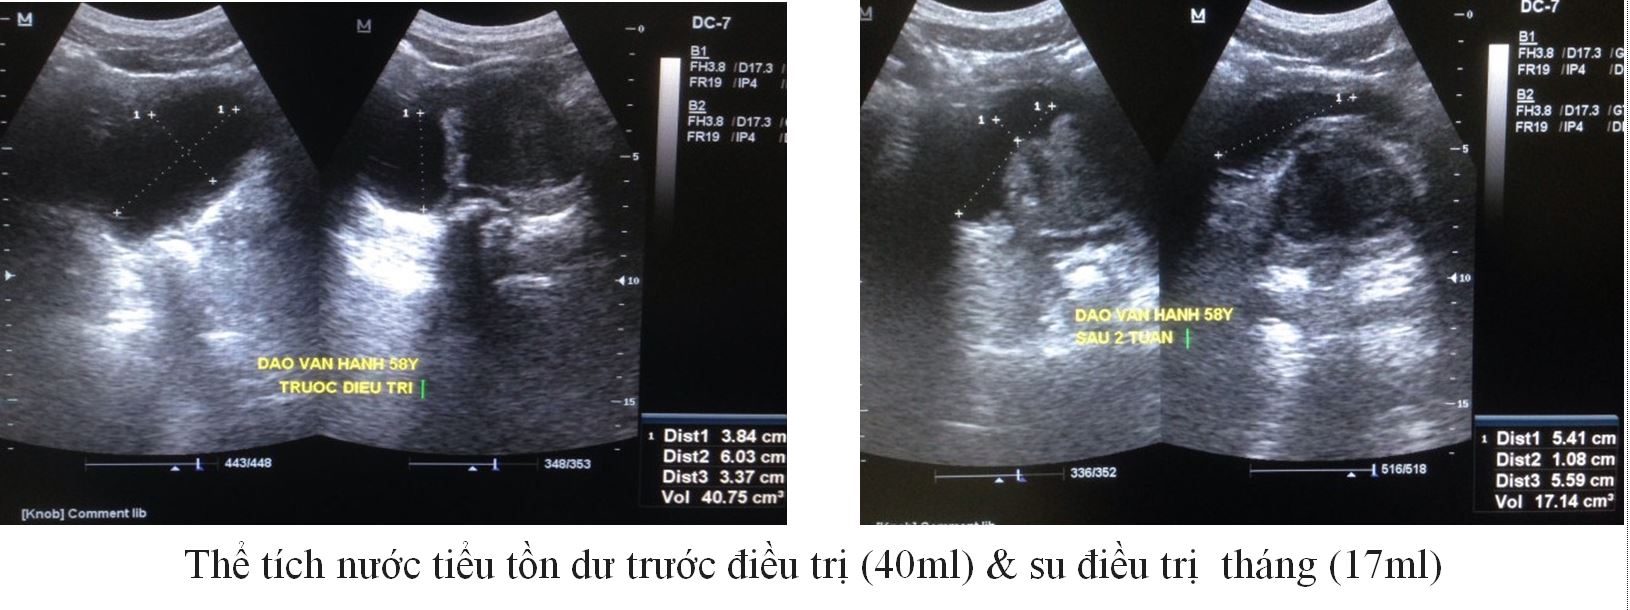

Trường hợp 2:

– BN: H, 58 Tuổi

– Tiểu khó, nhiều lần (3 lần trong đêm)

– Thể tích TLT 58 gam.

|

Trước ĐT |

Sau 1 tháng ĐT |

IPSS (Điểm) |

16 |

7 |

QoL (Điểm) |

3 |

1 |

PVR (ml) |

40 |

17 |

PV (gam) |

57 |

50 |

PSA (ng/ml) |

2,5 |

– |